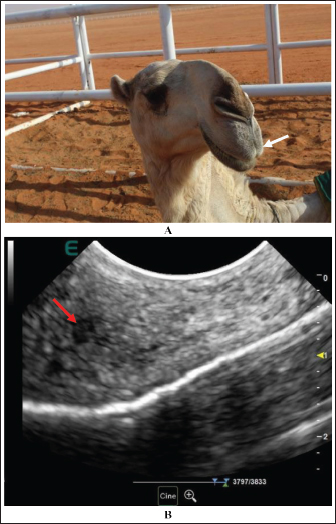

Extension and stretching of the lips in camels due to daily massage of the lips and sometimes binding with a rubber band resulted in blood congestion and lip enlargement (Fig. 7). Radiographic evaluation of filler materials in the perinasal region showed swelling of the soft tissues to the extent of variable degrees owing to the injected fillers; the injected substances appeared gray and had a soft tissue density (Fig. 8). In the injected lips, the injected filler was hypoechoic, and the scanning manner of the injected lips appeared heterogeneous (Fig. 9). In the perinasal area, the filler material appeared as either hypoechogenic or anechoic spots (Fig. 10). In infrared thermography (IRT), stretched lips appeared lighter and more heterogeneous than the darker and homogenous lips of healthy camels. In addition, the injected lip sites appeared darker than the surrounding tissue as their temperature was relatively higher when compared with healthy non-injected lip tissue (Fig. 11). Figure 12 shows a camel with enlargement of the lips due to filler injection, while Figure 13 shows enlargement of the soft palate or dulla and clitoris due to testosterone hormonal injection.

Fig. 9. A female camel with injected upper lip by a filler material. The upper lip is enlarged and pendulous (white arrow) (A). Sonographically, the injected substance appeared anechoic (red arrow), and the surrounding tissue appeared heterogeneous (B).